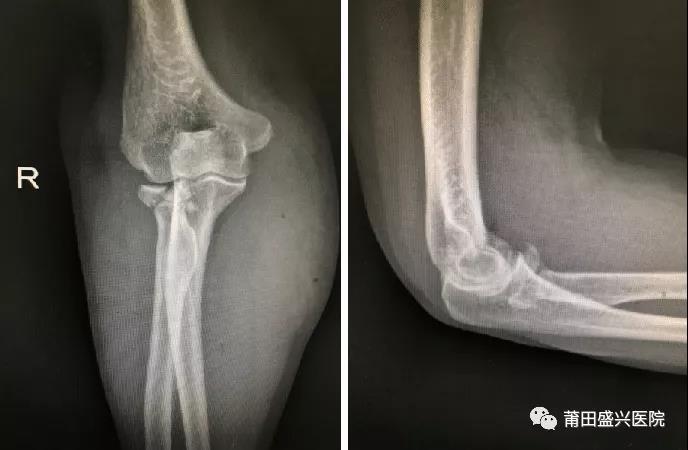

對(duì)于成人橈骨頭骨折Mason III型來(lái)說(shuō),橈骨頭就成為維持肘關(guān)節(jié)軸向和外翻穩(wěn)定的主要……